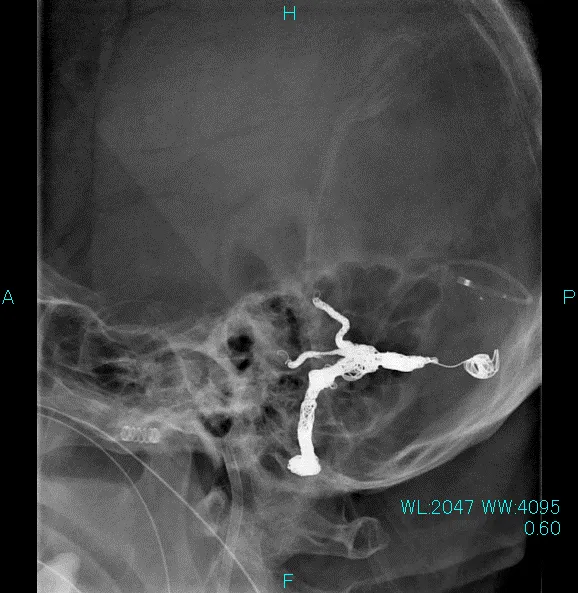

血管造影で左横静脈洞/S状静脈胴部硬膜動静脈瘻の診断

全身麻酔下にカテーテル治療(コイル塞栓術)を施行

数ヶ月のリハビリテーションの後、以前からの認知機能障害も改善し、自立した自宅生活が送れるようになりました。